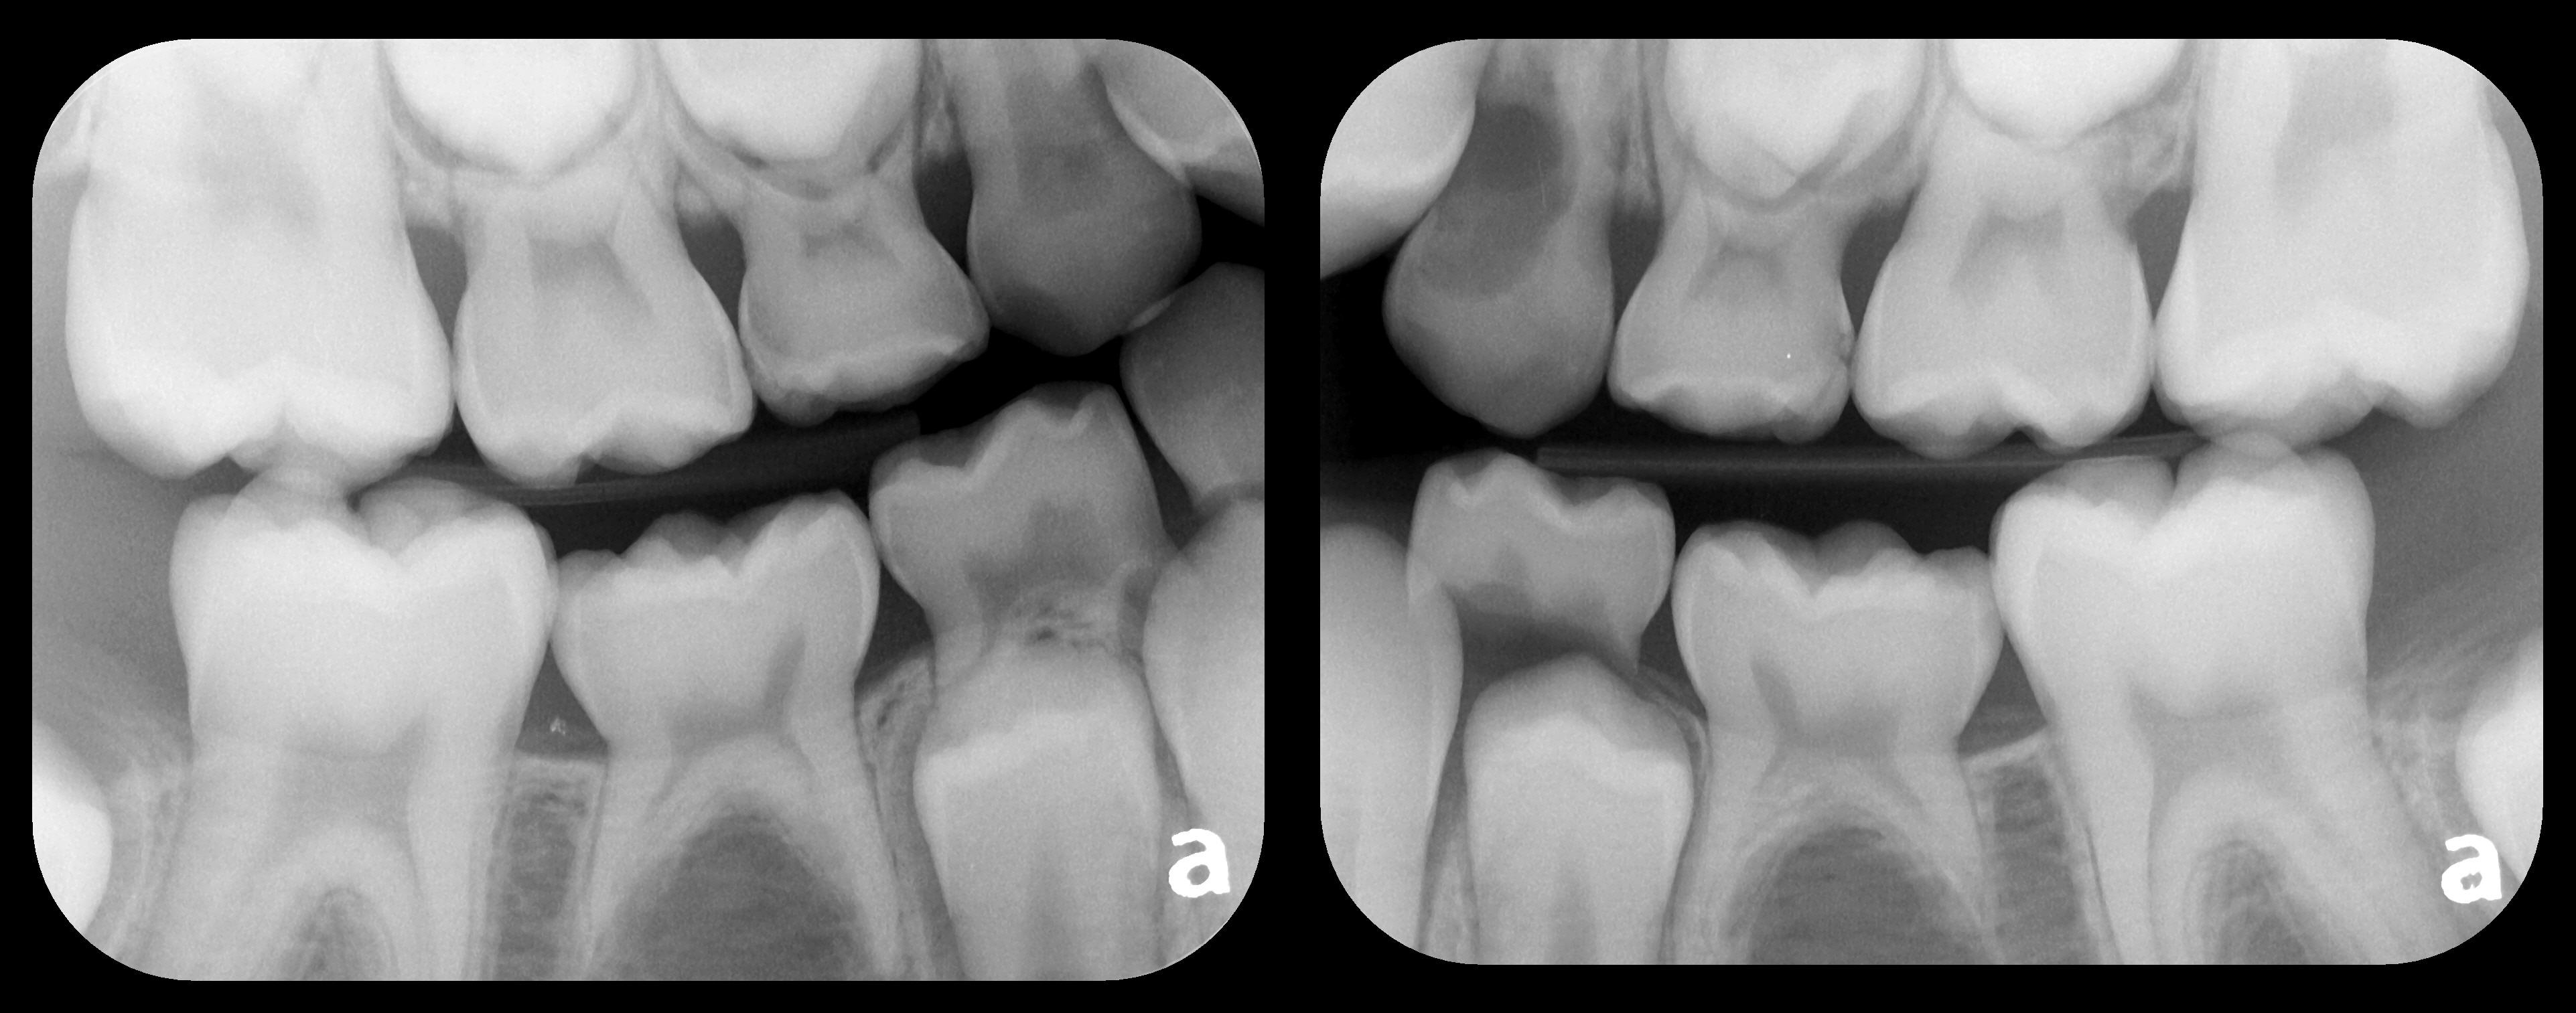

Fig 1. Left: Representative PSP BW radiograph with multiple restorative materials of varying radiographic densities. Tooth No. 31 demonstrates deep

caries on mesial aspect beneath the restorative. Radiolucency of carious lesion results from the low relative density of caries compared with healthy

tooth structure. Right: PSP BW radiograph optimized for view of multiple interproximal carious lesions.

Figure 1